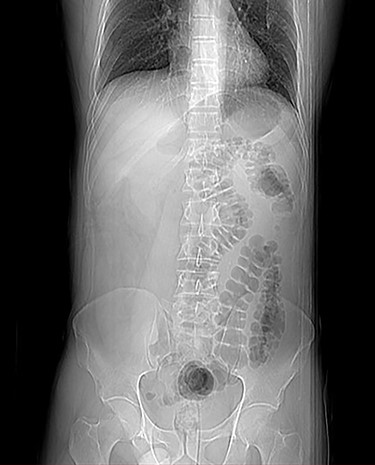

Two days later, for the persistence of symptoms, an abdomen computed tomography (CT) scan and surgical evaluation were required. The patient presented abdominal distension, tenderness without peritoneal signs, nausea and vomiting, but reported similar episodes auto-resolved abdominal in the past. The scan revealed a prominent gastrectasia, dilatation of duodenum and the first jejunal branch and jejunal mural edema was discovered, referable to an ischemic suffering, but there was no evidence of free air. The diagnosis was proximal bowel mechanical obstruction with suspect ischemic loop (Figs 2 and 3), so a surgical operation was proposed and the patients agreed.

The preoperative CT was reviewed, considering intraoperative findings, and an incomplete bowel rotation was highlighted: duodenojejunal loop was abnormally located on the right side of abdomen and cecum was positioned at the left of mesentery, as illustrated in Fig. 2.